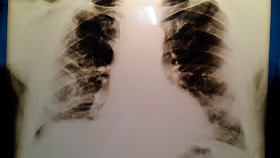

Rx de tórax parece haber una mayor densidad bibasal

que podría corresponder a densidades mamarias, pero sin signos de

redistribución de flujo ni otros signos de insuficiencia cardíaca.